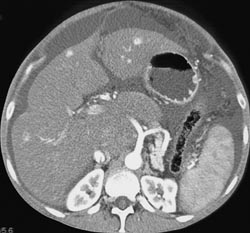

Hepatoma